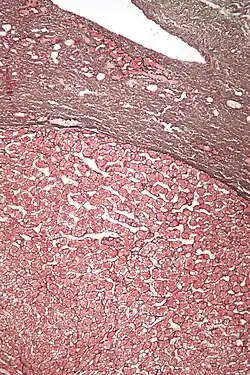

Micrograph of a hepatic adenoma (bottom of image). H&E stain | |

Pathologic diagnosis

Hepatic adenomas are, typically, well-circumscribed nodules that consist of sheets of hepatocytes with a bubbly vacuolated cytoplasm. The hepatocytes are on a regular reticulin scaffold and less or equal to three cell thick.

The histologic diagnosis of hepatic adenomas can be aided by reticulin staining. In hepatic adenomas, the reticulin scaffold is preserved and hepatocytes do not form layers of four or more hepatocytes, as is seen in hepatocellular carcinoma.

Cells resemble normal hepatocytes and are traversed by blood vessels but lack portal tracts or central veins.

Micrograph of hepatic adenoma. H&E stain